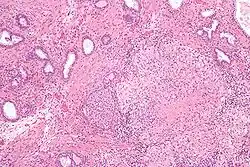

BCG vakcína je jednou z nejúspěšnějších imunoterapií.[24] BCG vakcína je „standardem péče o pacienty s rakovinou močového měchýře (NMIBC)“ od roku 1977.[24][25] Do roku 2014 bylo k léčbě neinvazivního karcinomu močového měchýře (NMIBC) používáno více než osm různých biosimilárních látek nebo kmenů.[24][25]

- BCG vakcína se používá při léčbě povrchových forem rakoviny močového měchýře. Od konce 70. let jsou k dispozici důkazy, že vštípení BCG do močového měchýře je účinnou formou imunoterapie u tohoto onemocnění.[26] Zatímco mechanismus je nejasný, zdá se, že proti nádoru je vyvolána lokální imunitní reakce. Imunoterapie s BCG zabraňuje recidivám povrchového karcinomu močového měchýře až v 67 % případů.